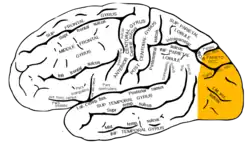

Lóbulo occipital

El lóbulo occipital es uno de los seis lóbulos principales,[1][2][3] de cada hemisferio del cerebro.

El lóbulo occipital da forma a la parte posterior de cada hemisferio cerebral llamada polo occipital y no está claramente separado mediante surcos de los lóbulos parietal y temporal.[6]

El lóbulo occipital muestra una forma piramidal con vértice posterior en el polo occipital. Su cara lateral externa es convexa, su cara interna o medial es plana y su cara inferior es ligeramente cóncava.

Cada lóbulo occipital, se divide en varias áreas de función visual.